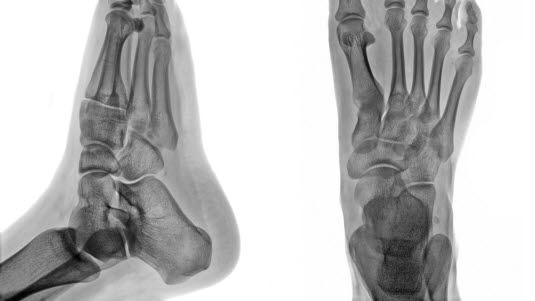

1. Os calcaneus (hælbenet) 2. Os cuboideum (terningbenet) 3. Os cuneiforme laterale (laterale kileben) 4. Os cuneiforme mediale (mediale kileben) 5. Os naviculare (båtbenet) 6. Os talus (ankelbenet) 7. Os fibula (det lille leggbenet) 8. Os tibia (skinnebenet)Ankelartrose er betegnelse på slitasjeforandringer (artrose) i ankelleddet. Slike forandringer er vanligvis bare lokalisert til den ene foten. Ankelleddet består av beinflater som er dekket med et lag brusk. Ved begynnende slitasje er det brusken som først blir slitt. Med tiden kan brusken bli så nedslitt at bein gnisser mot bein. Det kan også dannes ujevnheter og forkalkninger i leddet. Dette medfører at det ikke lenger er glatte leddflater som glir mot hverandre, og da blir bevegelsene i leddet smertefulle.